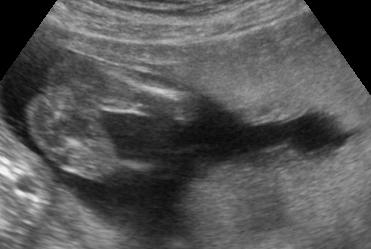

Ui.: Kedden megyünk genetikai UH-ra, szorítsatok nekem. Aztán majd jelentkezem.